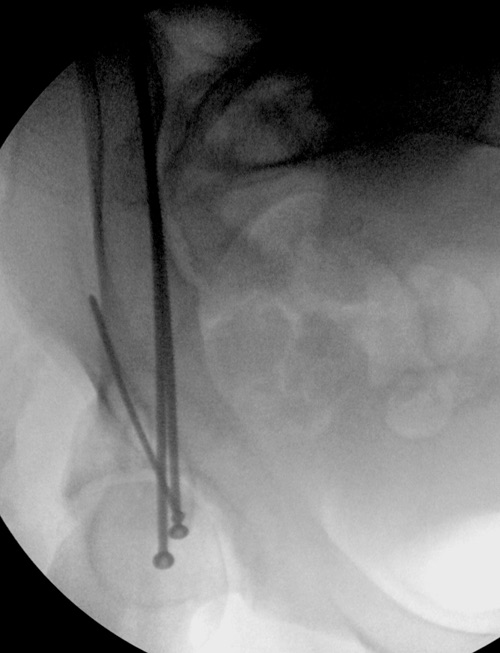

Здесь пример перелома передней стенки, где сохранен принцип фиксации

передней колонны. Для доступа Smith Petersen с остеотомией ASIS. Мышца

сарториус отодвинута, и сделана ре-фиксация на свое место винтами. При

хорошем обзоре, наличие Farabeuf или Jungblud forceps облегчит репозицию.